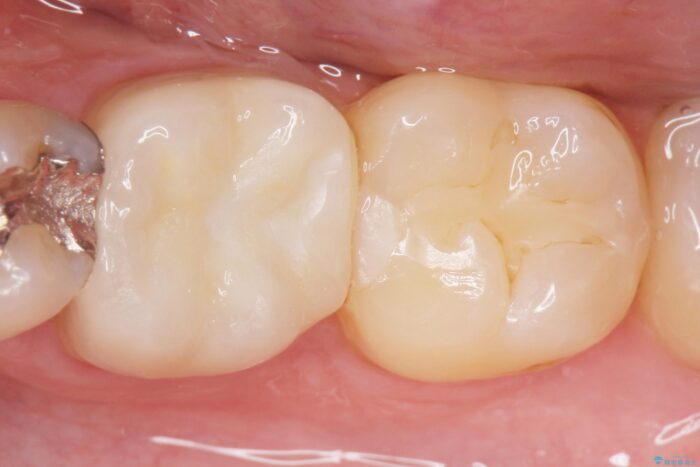

食べ物がよく詰まる、見た目も悪いので銀歯をやり替えたいとご来院された患者様です。

歯と歯の間に食べ物が詰まったままの状態だと、虫歯や歯周病を誘発しやすいため、注意が必要です。